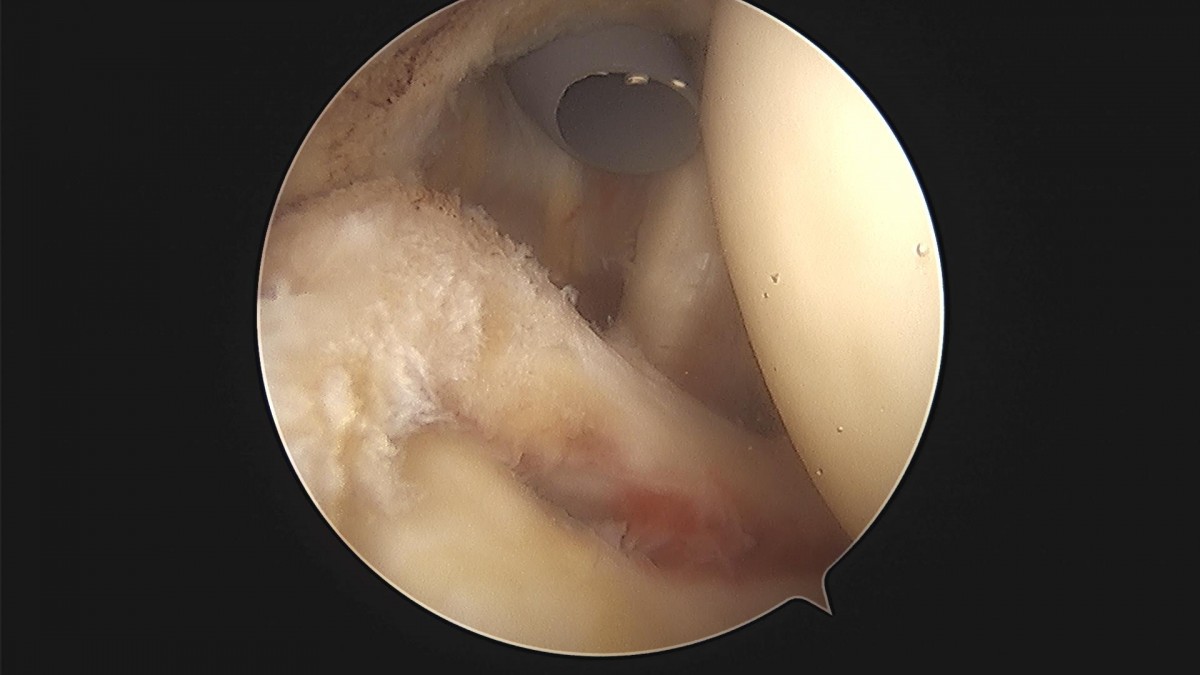

이재상 원장님 어깨 관절낭 이완술 견봉성형술 정순O 환자

d4279b3b94d98ed627b1644855bcf9f2_1699600708_6302.jpg

d4279b3b94d98ed627b1644855bcf9f2_1699600708_9325.jpg

d4279b3b94d98ed627b1644855bcf9f2_1699600709_2323.jpg

d4279b3b94d98ed627b1644855bcf9f2_1699600709_5791.jpg

d4279b3b94d98ed627b1644855bcf9f2_1699600709_935.jpg

d4279b3b94d98ed627b1644855bcf9f2_1699600710_2459.jpg

d4279b3b94d98ed627b1644855bcf9f2_1699600710_5528.jpg

d4279b3b94d98ed627b1644855bcf9f2_1699600710_8577.jpg

d4279b3b94d98ed627b1644855bcf9f2_1699600711_1836.jpg

d4279b3b94d98ed627b1644855bcf9f2_1699600711_4993.jpg